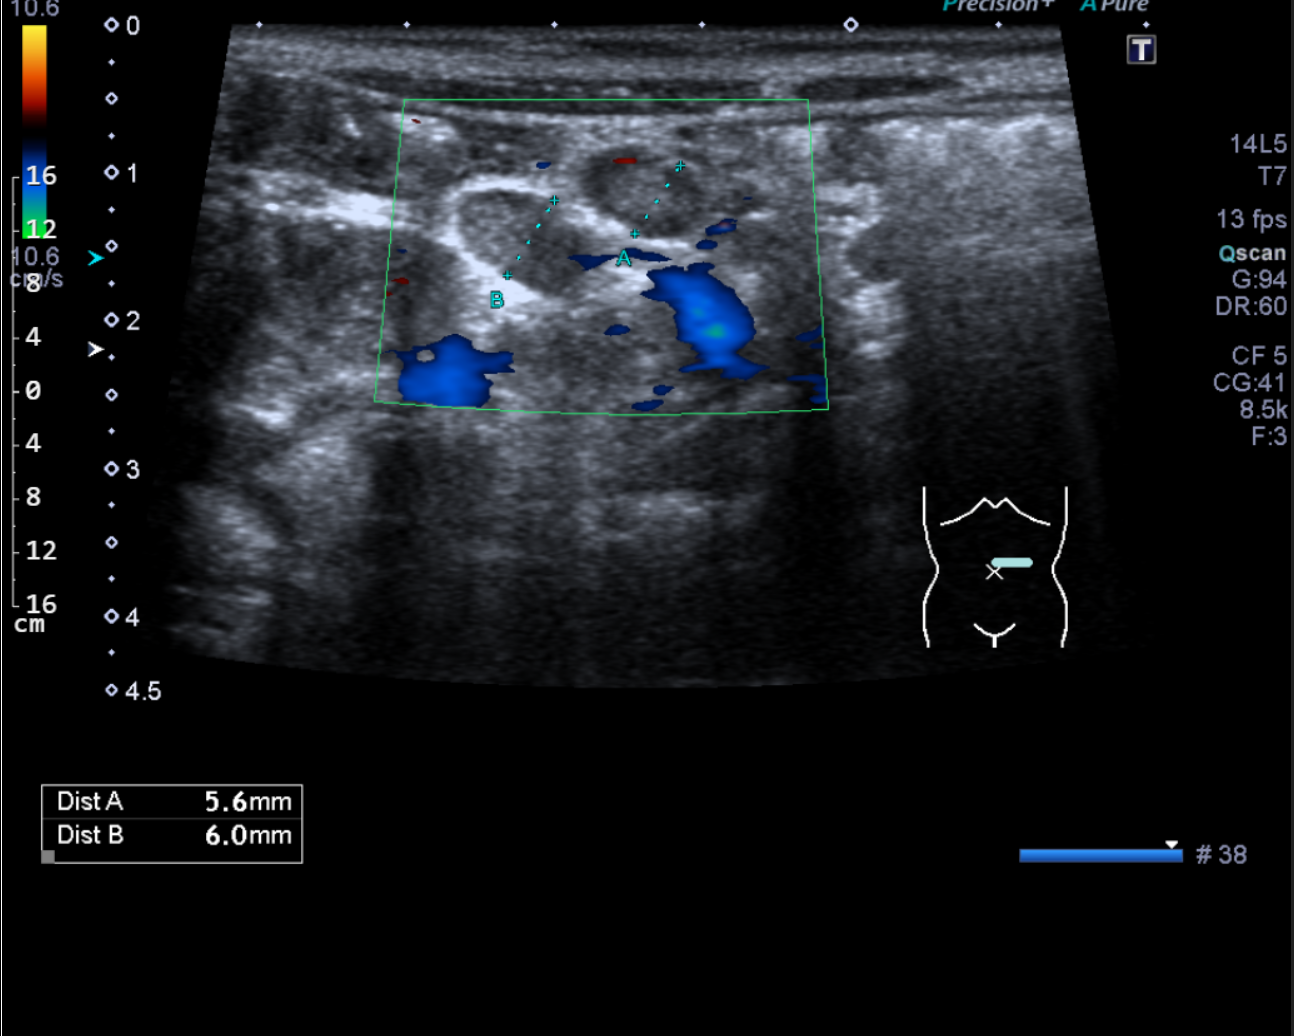

Dopplerovské ultrazvukové vyšetření navíc umožňuje kvalitativně i kvantitativně posoudit nález na cévním řečišti, zejména zhodnotit přítomnost uzávěrů cév či posoudit stupeň jejich zúžení.

Zjednodušeně řečeno je indikací ultrazvukového vyšetření posouzení morfologického nálezu ve vyšetřované oblasti. Tedy odpověď na otázku, zda je v problematické oblasti něco divného a pokud ano, o co se jedná. Ultrazvuk je velmi vhodnou metodou pro posouzení orgánů v břišní dutině a v měkkých tkáních krku i jinde na těle, naopak je prakticky nepoužitelný pro posouzení plic a kostí. Dopplerovský ultrazvuk umožňuje hodnotit nález na cévách, zejména posoudit jejich průchodnost a eventuelně stupeň zúžení, které bývá nejčastěji na podkladě aterosklerózy (kornatění tepen).

Vyšetření provádí erudovaný lékař, který pro danou vyšetřovanou oblast zvolí vhodnou ultrazvukovou sondu a nastaví optimální parametry přístroje. Pacient při vyšetření leží na vyšetřovacím stole a dodržuje pokyny lékaře. Nejčastěji se vyšetření provádí vleže na zádech, na břiše nebo na boku. Kůže pacienta se ve vyšetřované oblasti pokrývá vrstvou gelu pro sonografii. Lékař plynule pohybuje po pacientově těle ve vyšetřované oblasti ultrazvukovou sondou a při tom sleduje obraz na monitoru. Vyšetření se provádí v různých rovinách daných postavením sondy, někdy i v různých polohách pacienta. Během vyšetření lékař v případě potřeby provádí různá měření. Při vyšetření asistuje vyškolená sestra, která pomáhá především s odstrojením a uložením pacienta, provádí administrativní úkony a řídí objednávání pacientů. Před vyšetřením sestra nebo lékař vysvětlí pacientovi stručně, jak vyšetření probíhá a co je jeho cílem, eventuelně rozptýlí případné obavy pacienta z vyšetření. Na závěr vyšetření pak lékař pacientovi co nejsrozumitelněji vysvětlí zjištěný nález, jeho závažnost a případné další důsledky. Obrazová dokumentace je zhotovena tiskem na speciální papír, eventuelně je provedena digitální archivace obrazu.

Ultrazvukový přístroj

Naše pracoviště je vybaveno přístrojem Aplio 300 od firmy Toshiba, který je vybaven konvexními a lineárními sondami.